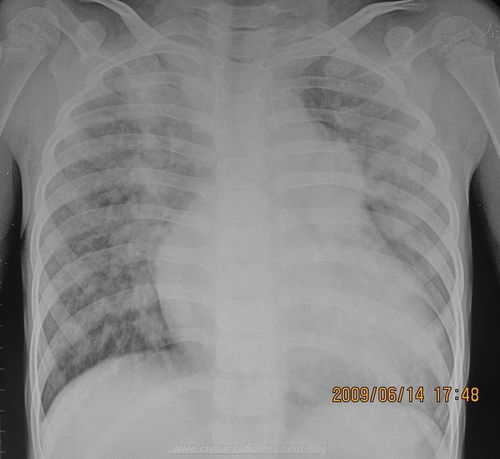

胸透可以看到胸部的軟組織、骨骼(包括胸椎)、縱隔(心臟、大血管、氣管、食管等)、氣管和支氣、胸膜、肺組織等??梢栽\斷肺和氣管的先天性疾病,如發(fā)育異常、肺部的各種炎癥、急慢性支氣管炎、比較明顯的支氣管擴張癥、肺氣腫或肺水腫、各型肺結核、肺腫瘤、胸腔積液、氣胸、縱隔腫瘤、心臟形態(tài)異常等

健康查體最常做的是胸部的X線(xiàn)檢查,最基本的就是胸透。 胸透可以看到胸部的軟組織、骨骼(包括胸椎)、縱隔(心臟、大血管、氣管、食管等)、氣管和支氣、胸膜、肺組織等。

可以診斷肺和氣管的先天性疾病,如發(fā)育異常、肺部的各種炎癥、急慢性支氣管炎、比較明顯的支氣管擴張癥、肺氣腫或肺水腫、各型肺結核、肺腫瘤、胸腔積液、氣胸、縱隔腫瘤、心臟形態(tài)異常等。